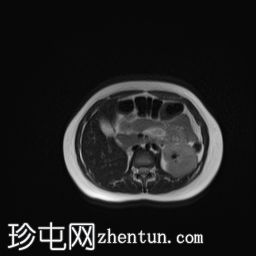

MRI

矢状位

T2加权像

子宫腔重复畸形,表现为两个子宫体和两个宫颈。

右侧宫颈和子宫腔明显扩张,内部血流信号显示中央狭窄,T1加权像呈高信号,T2加权像呈低信号,脂肪抑制序列图像上无信号下降,内部可见持续低信号灶。最大轴位和冠状位直径分别为约6.5 x 6.4 x 14.2 cm。可见该肿块向前压迫膀胱,向后推移右侧卵巢,并紧贴左侧宫颈。

左侧子宫系统未见扩张,未见与左侧子宫腔相通的迹象。

双侧重复子宫腔的交界区完整,未见明显的肌层局灶性病变。左侧子宫内膜厚度正常。

可见两个阴道腔,共同远端开口长1.6厘米。